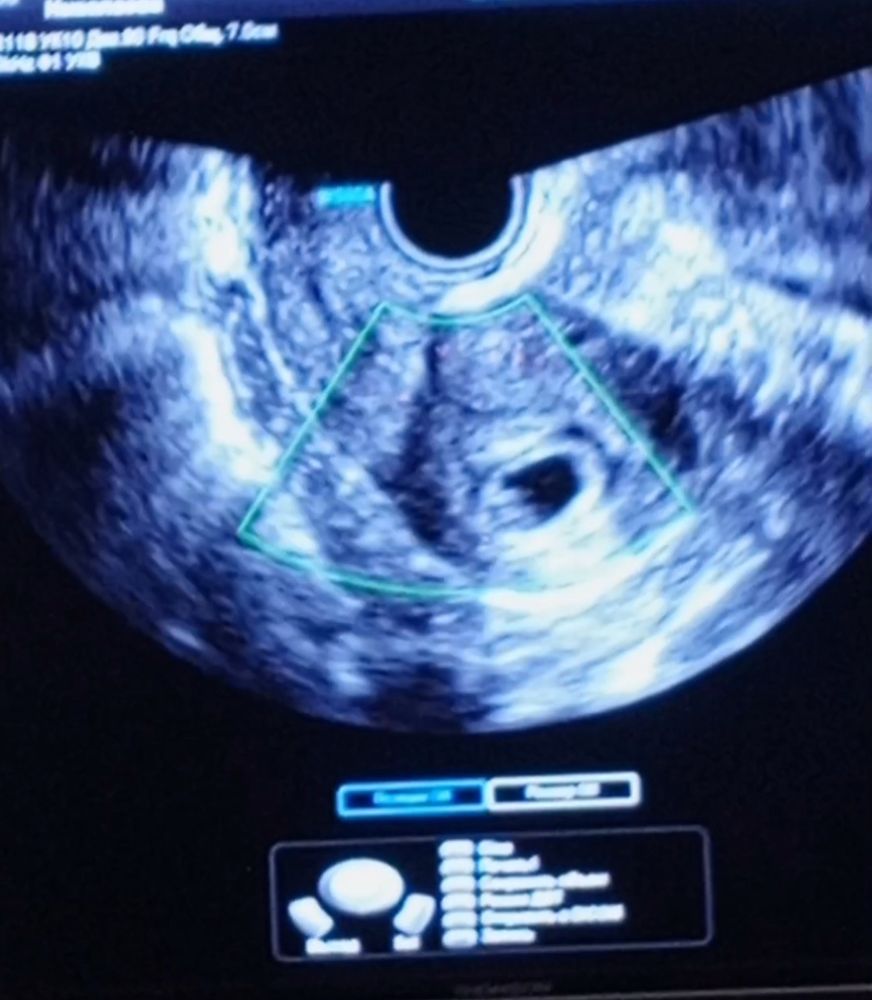

Результаты: УЗИ, КТГ, доплера, скринингаДевочки вообщем привет , про эту беременность я не писала здесь , но уже нет сил. В 5 недель и 1 день я попала с кровотечением в больницу , но ни отслоек ни гематом. Выписали всё ок. 24 мая было 6 недель и 5 дней. Съездила в роддом где отец мужа работает на узи сердцебиение послушать все супер. Прилагаю фото (синее сделано 24 мая, эмбрион 8.3)